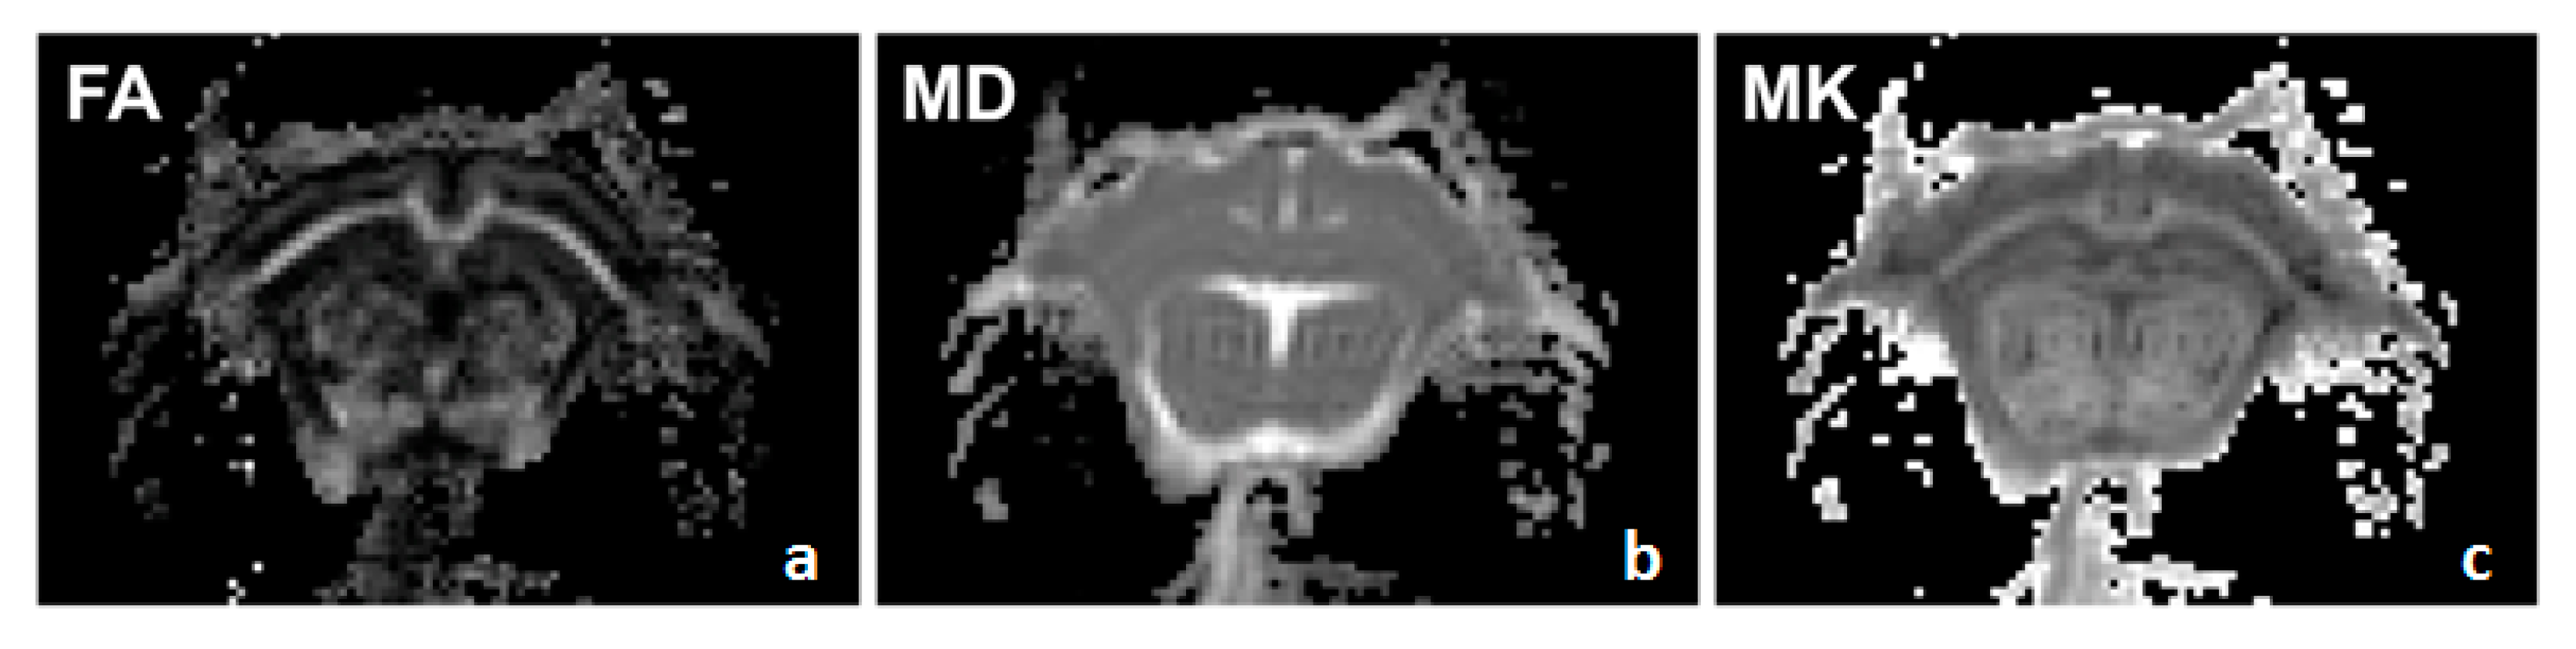

2.2. In Vivo MRI

2.3. Data Processing